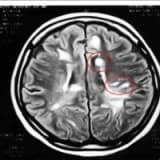

Ozon Tedavisi